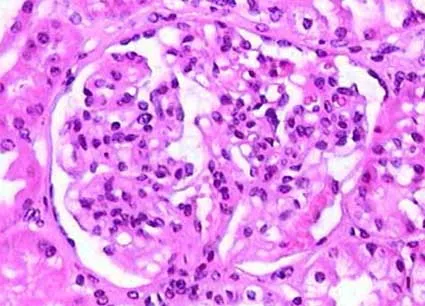

Injúria Renal Aguda (revisão Lancet 2025)